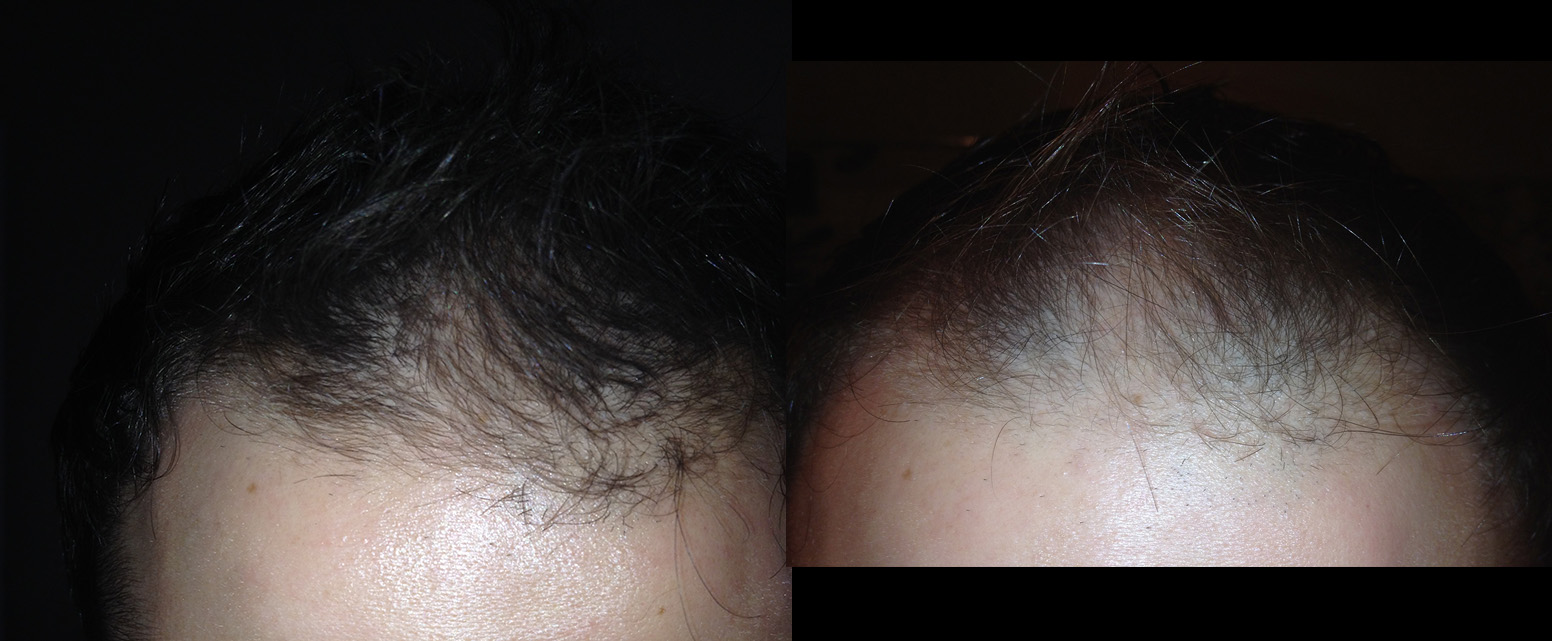

Here is my current situation, left is last week and right is August 2014. Im in the same room, same lighting, hair is the same length, and flash is on on my camera. You can use the brown freckle on the left side of my upper forehead as a way to see my hair line difference. Which isnt much right now but the diffuse growth is whats really noticeable here.

Here is my current situation, left is last week and right is August 2014. Im in the same room, same lighting, hair is the same length, and flash is on on my camera. You can use the brown freckle on the left side of my upper forehead as a way to see my hair line difference. Which isnt much right now but the diffuse growth is whats really noticeable here.